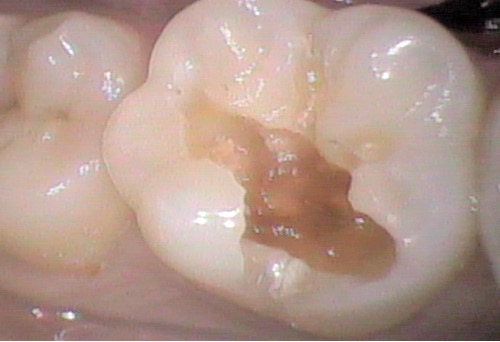

CR前↓ CR後↓

CRとは、小さな虫歯や欠けた歯などをプラスチックの素材で充填していく治療方法です。

歯の色に合わせて調整でき、通常は1回の治療ですみます。

写真は削った時に歯の中の方で虫歯が広がっていましたが、CR後はわからないくらい綺麗になってますよね(*^^*)